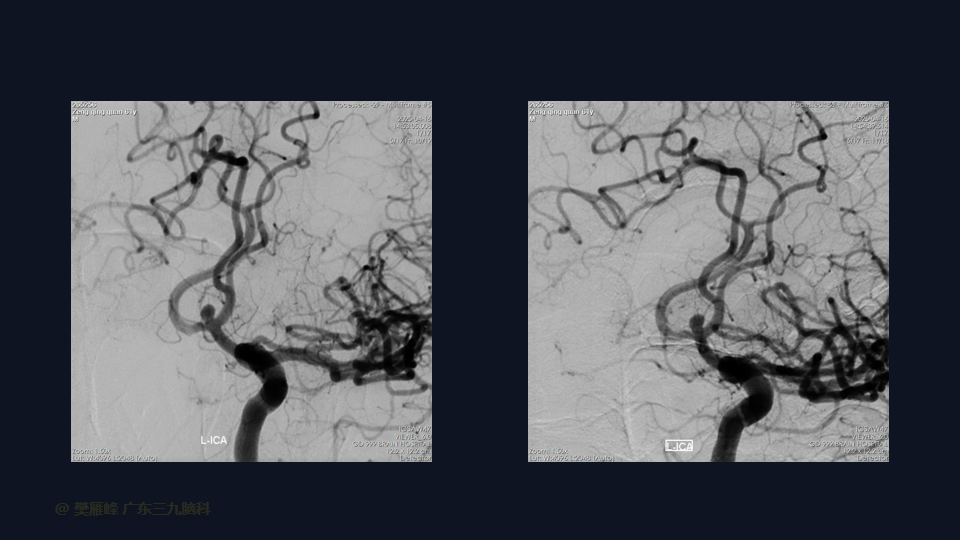

在这个二维手术视频中,展示了一种经翼点入路显微夹闭未破裂的前交通动脉瘤的方法。患者是一名61岁的男性,发现前交通动脉瘤1年较前增大,神经影像学显示前交通动脉大小约为3.6×3.3mm的囊状突起影。他接受了开颅手术夹闭动脉瘤的方法,术中血管造影显示动脉瘤完全夹闭。术后无新发神经功能。我们展示了细微的动脉分离技术和动脉瘤夹闭技术的细微差别和技术要点,以及手术技术。